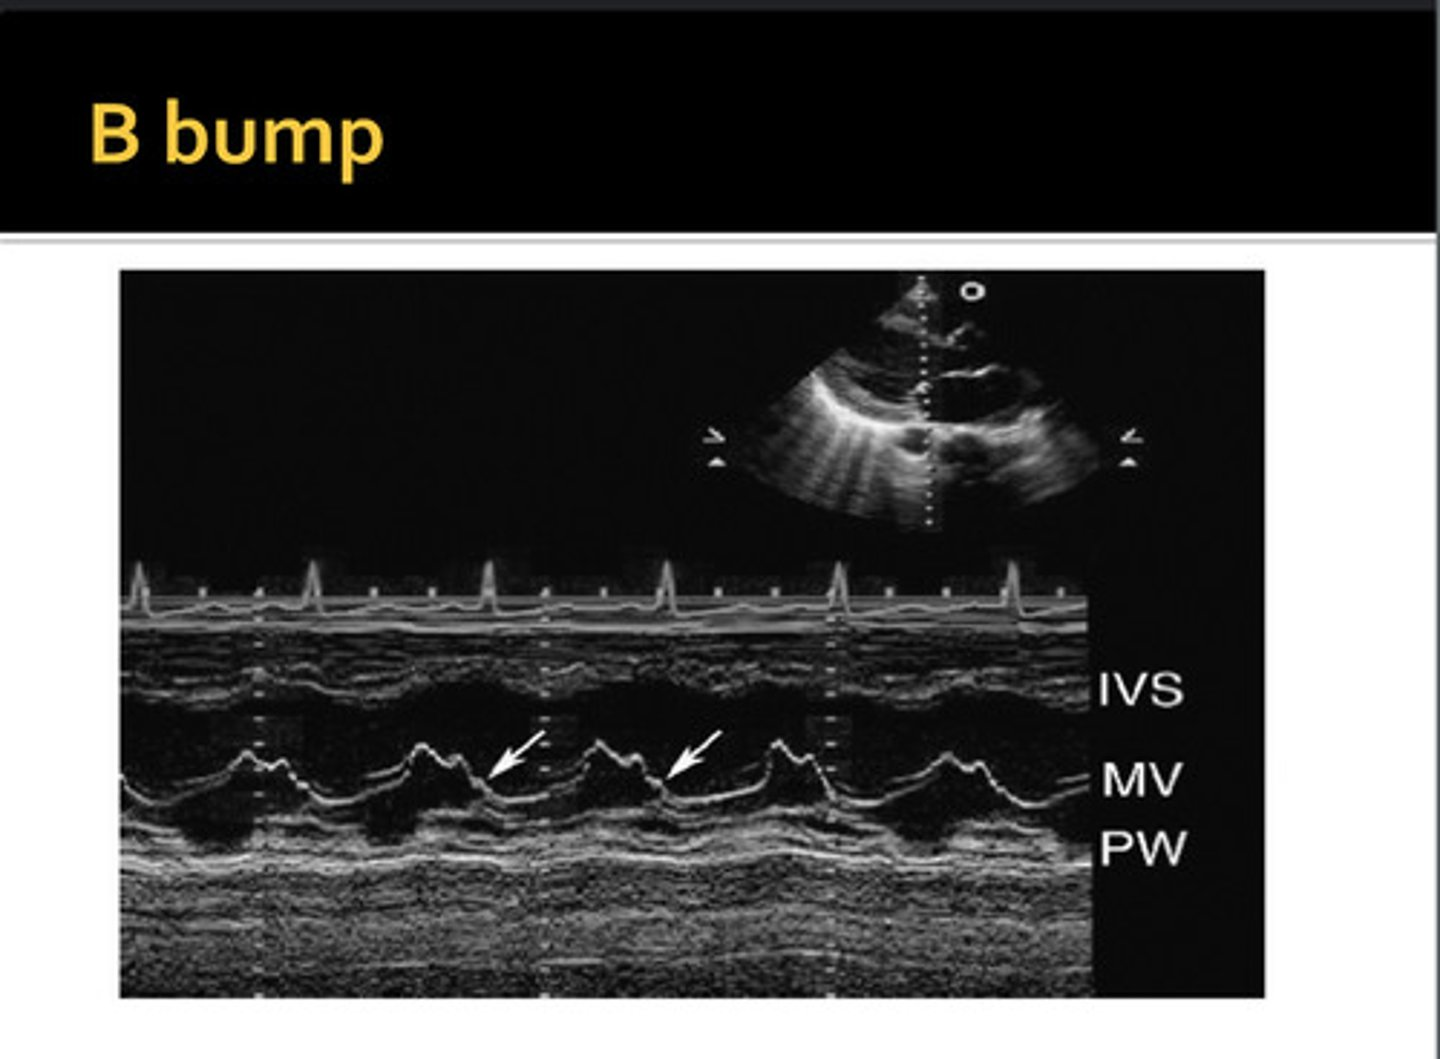

extra hump between A-C; commonly seen with dilated cardiomyopathy and LV dilation; increased LVDP and LA pressure; decreased EF% and EPSS is >10mm

B-Bump/B-Notch/ A-C Shoulder